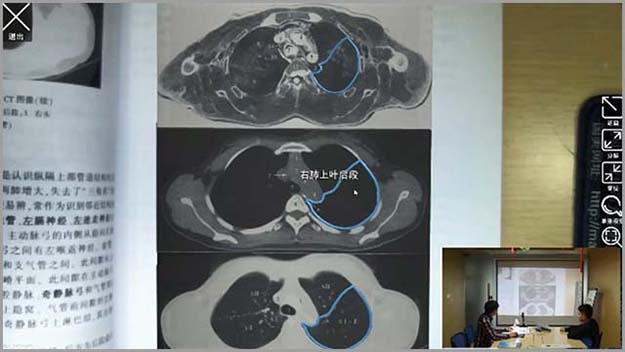

基礎醫(yī)學系列-增強現(xiàn)實醫(yī)學影(yΩ↑∏πǐng)像應用(yòng)解剖學

增強現(xiàn)實醫(yī)學影(yǐng)像應用(yòng)解剖學